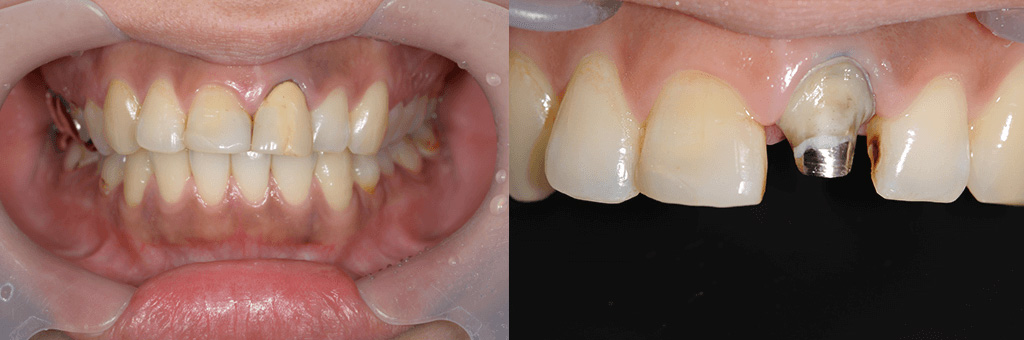

図5

左上の前歯の色が気になり、来院されました。過去に装着された被せ物を外したところ、金属の土台が装着されていました。透明感を再現するためにセラミッククラウンを装着したいケースですが、透明感を出しすぎると内部の金属の色が透けてしまうので、難しいケースと言えます。